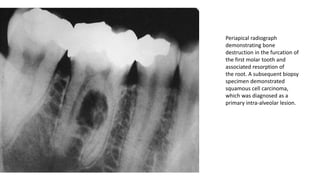

Periapical radiograph

demonstrating bone

destruction in the furcation of

the first molar tooth and

associated resorption of

the root. A subsequent biopsy

specimen demonstrated

squamous cell carcinoma,

which was diagnosed as a

primary intra-alveolar lesion.